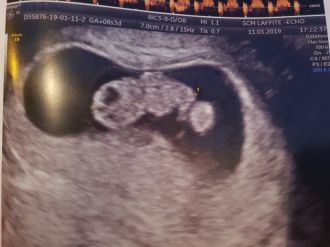

Nous sommes le vendredi 11 janvier et je trépigne.

Cette journée n'avance pas assez vite.

J'ai rendez-vous à 15h30 pour mon écho de datation.

Je suis trop pressée mais .... le temps n'avance pas !

Enfin, il est l'heure d'aller rencontrer (je l'espère !) notre petit bébé qui pousse !

L'attente est longue. Il y a du monde.

Nous ne passerons finalement qu'à 17h30 mais une fois sur la table d'écho, on oublie tout.

Il allume l'appareil.

Je me surprends à croiser les doigts.

Jérôme fixe l'écran et attend.

Il attend de le voir.

Un bébé, un cœur qui clignote.

Puis tout à coup, il est là.

Je le vois <3

Il mesure 19,27 mm du sommet du crane jusqu'au bout des fesses.

Les larmes montent. Je vois le cœur qui clignote.

"Ouf".

Le gynéco pousse un bouton pour l'écouter.

Le rythme est lent, trop lent.

Le bonheur redescend vite.

"Et merde".

Heureusement, il me dit qu'il l'a juste perdu.

Il replace la sonde et là, on entend son petit cœur qui bat la chamade.

Je suis définitivement rassurée.

Je suis heureuse, je suis enceinte <3 <3 <3